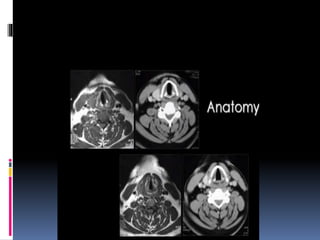

CORONAL CUTS

 One should study the scout film first

The coronal cuts should be read from

anterior to posterior.

The most anterior cuts show frontal sinus

and nasal bone.